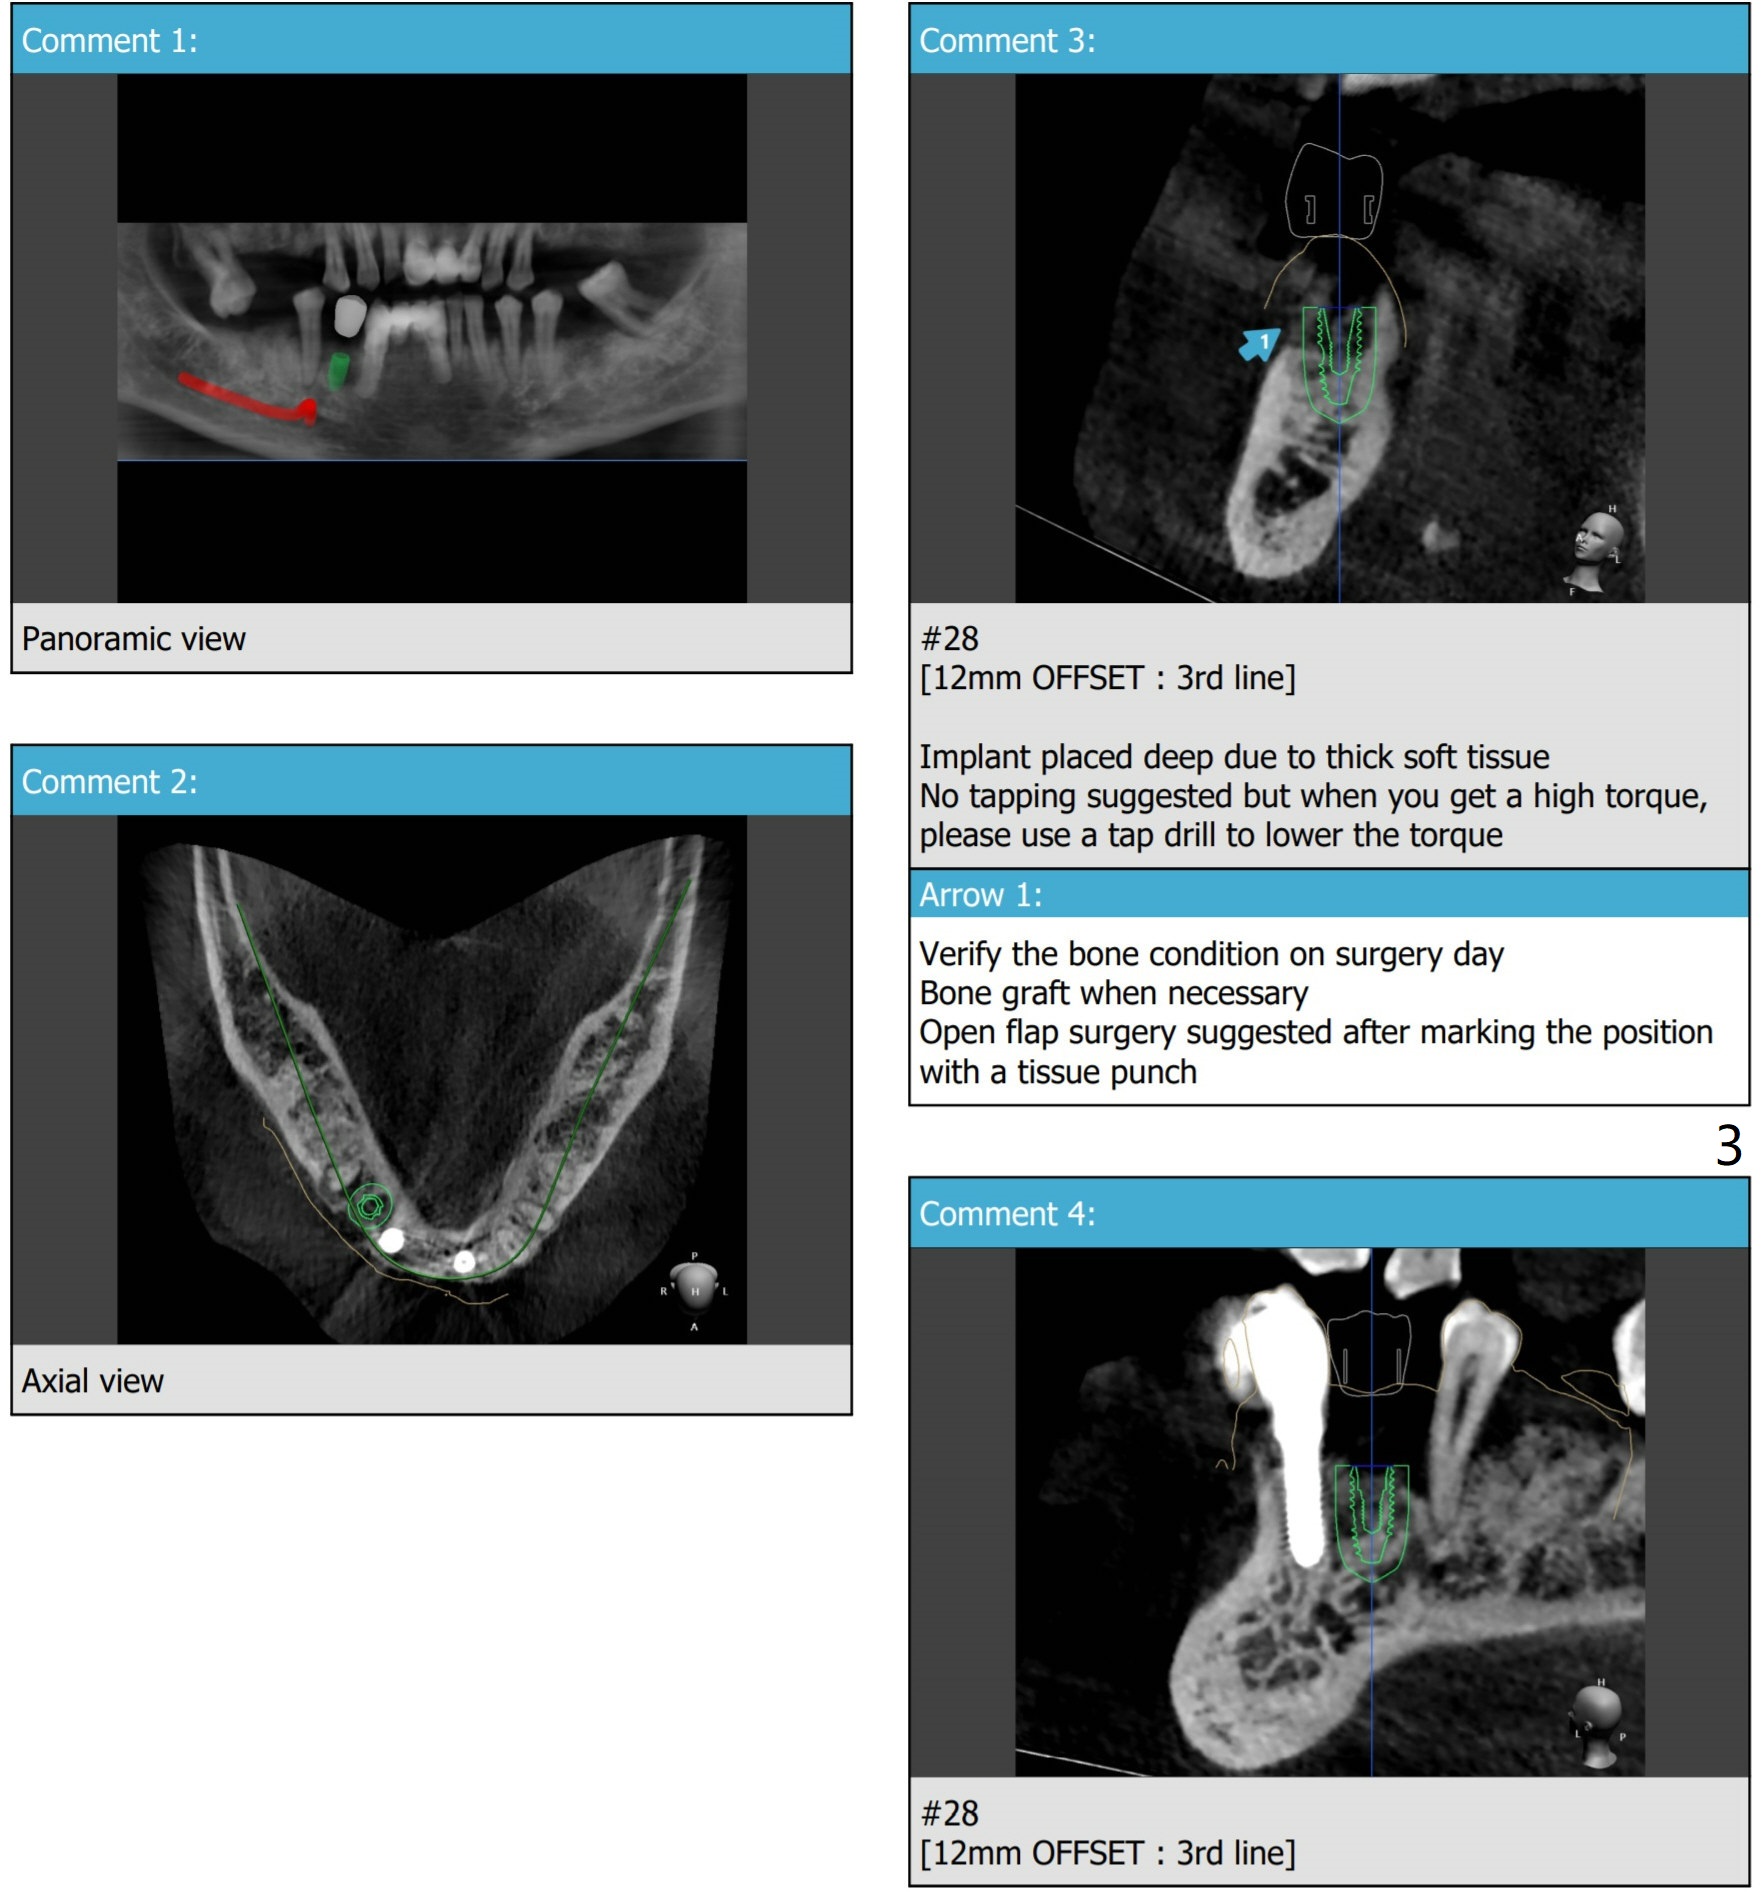

植骨低骨密度

53岁男,左下4(28号牙)需要植牙,拔牙而没有植骨后一年,由于牙槽窝骨质密度不均匀,可能低。稍微使用环形钻头后,形成标记,切开探查,使用自体骨做必要植骨:植牙区和第二前磨牙近中。植入FC植体4.5x11毫米,可以稍微浅:.5-1.0毫米,同时减少牙龈厚度,颊侧放置骨粉